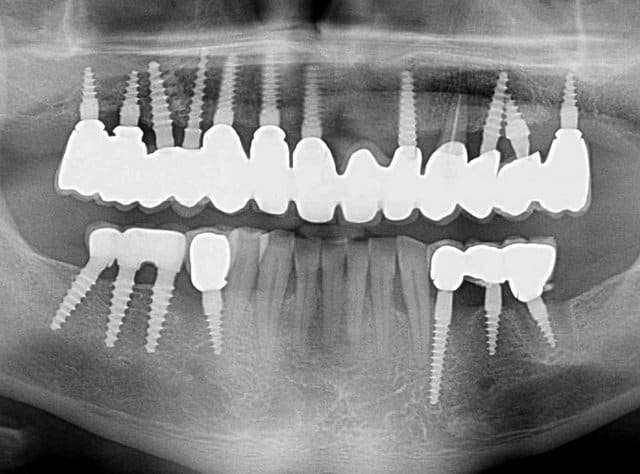

23 implants, rehabilitation totale

Bonjour flicflac je suis désolé de ma réponse tardive, oui il est vrai que ce n est pas beaucoup documenté ... je serai un menteur de dire que que je n ai jamais perdu des implants, surtout entre la 2eme et 8eme semaine après l implantation.Un échec vraiment à cause de la perte osseuse et avec le même process cela est arrivé une fois avec une madame, où l´os était encore infecté ( avant la chirurgie),mais après l ´échec (c était à la position 35) on a pu laisser le bridge. Malheureusement je n ai pas toutes les photos ici à Mallorque sur mon PC portable. Ci dessous une photo après 10 ans 46 47 et les implants au maxillaire.

23 opg komplett zcukva - Eugenol